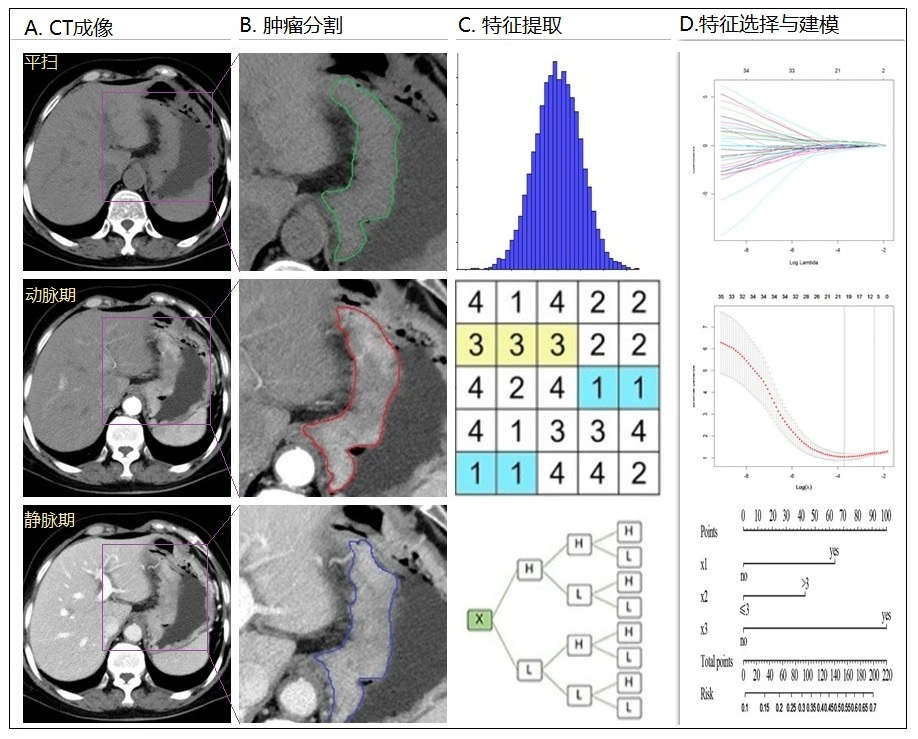

图5 基于影像组学建立模型的流程图